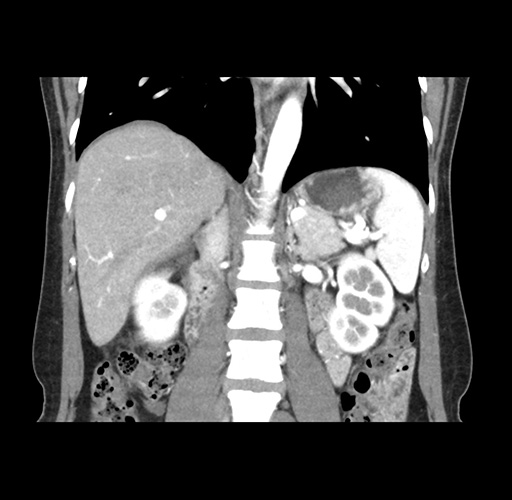

Imaging Analysis

Look through the patient's CT scan to identify any areas of concern for the necessary procedure.

Based on your CT findings, which issue(s) would give reason for "planned slowing down moment(s)" in this case?

Considering a standard left lateral sectionectomy procedure, what step(s) of the operation would you do differently in this case ?